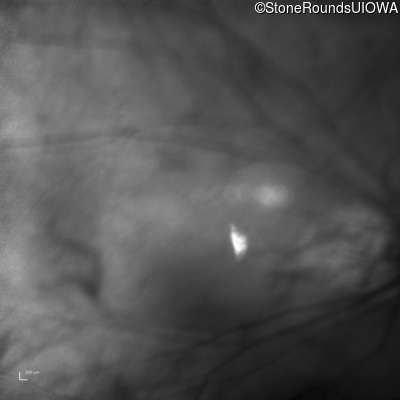

Age at visit: 32 years